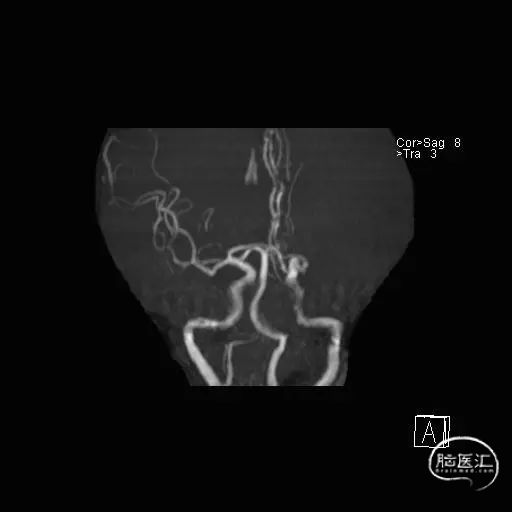

MRA:左侧大脑中动脉闭塞。

术前DSA影像

左侧颈内动脉造影—M2段闭塞。